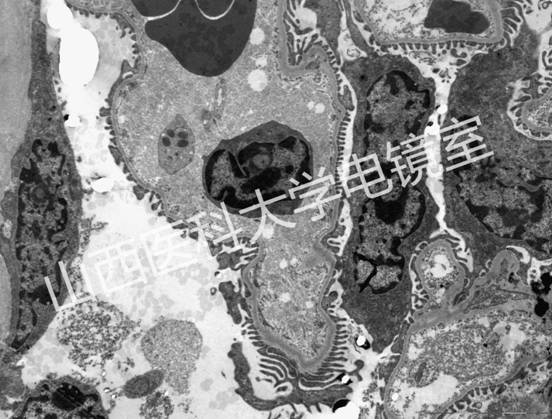

代表性圖譜:

破骨細(xì)胞